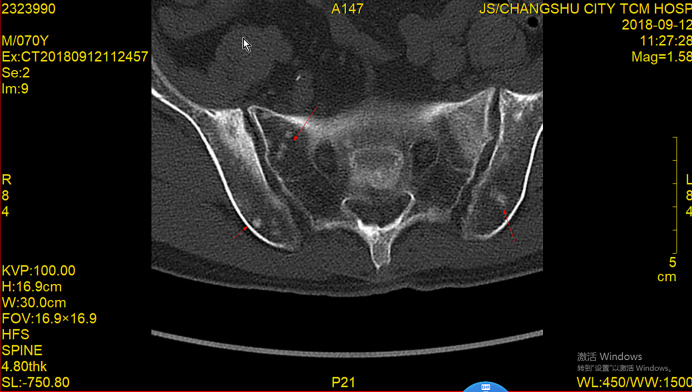

前列腺癌是男性最常见的恶性肿瘤之一,骨转移是常见的并发症,严重影响患者的生活质量和生存率。病例介绍:本文报道一例前列腺癌多发骨转移患者在化疗联合内分泌治疗后完全缓解并存活6年。结论:本文通过详细介绍患者的治疗过程及随访结果,探讨化疗联合内分泌治疗在前列腺癌骨转移治疗中的应用价值。

Case presentation: This article reports a case of a patient with multiple bone metastases from prostate cancer who achieved complete remission and survived for 6 years following chemotherapy combined with endocrine therapy.